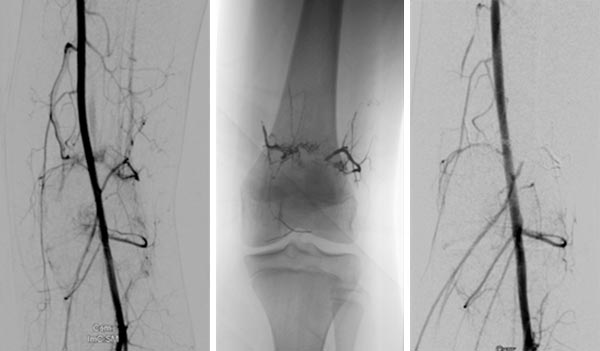

Further stepwise embolization of the main areas of the arteriovenous malformation, here at the knee. The cast specimen caused by the radiopaque embolization material (ethylene-vinyl alcohol copolymer) shows the occlusion down to the smallest vessels.

DSA before embolization (left) shows multiple fine AVMs near the knee joint. In the non-subtracted radiograph after embolization, the radiopaque embolic agent can be seen (middle), completely filling the arteriovenous fistulas. In DSA after embolization (right), the entire nidus of the AVM is occluded, no more arteriovenous fistulas are visible.

This disease course in a child with Parkes-Weber syndrome shows some typical characteristics of the clinical picture. It diffusely affects an entire limb and shows multiple, very fine fistulous arteriovenous fistulas in the sense of an extensive arteriovenous malformation (AVM). Concomitantly, the affected limb is not only enlarged due to edema from the increased venous pressure, but there is also concurrent true hyperplasia of all tissues of the affected limb. Extensive embolization is indicated when venous pressure becomes too great and significant discomfort or marked skin manifestations occur. In addition, temporary epiphysiodesis is often necessary in children due to progressive leg length discrepancy. Before insertion of the staples or "eight-plates" for temporary growth inhibition, the parts of the AVM close to the knee joint must be occluded, as was the case in this patient, in order to allow the osteosynthesis material to be inserted and removed without complications and blood loss.